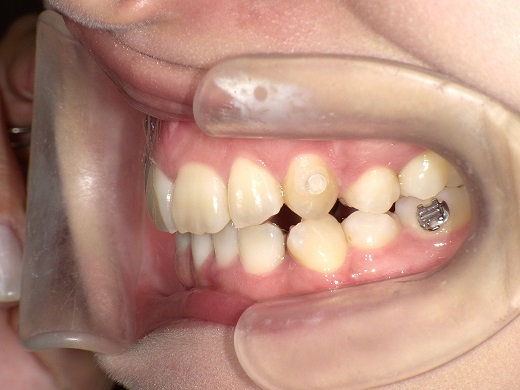

治療前右側

治療中右側